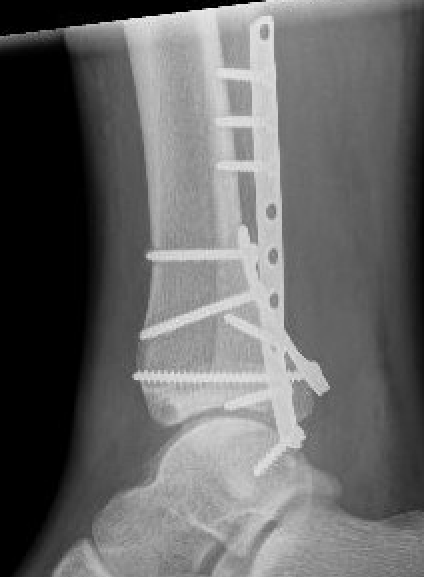

Tri-Malleolar Fracture

Lateral malleolus + medial malleolus + posterior malleolus

Posterolateral approach

- prone or lateral

- ORIF fibula + posterior malleolus

- move patient to supine to ORIF medial malleolus